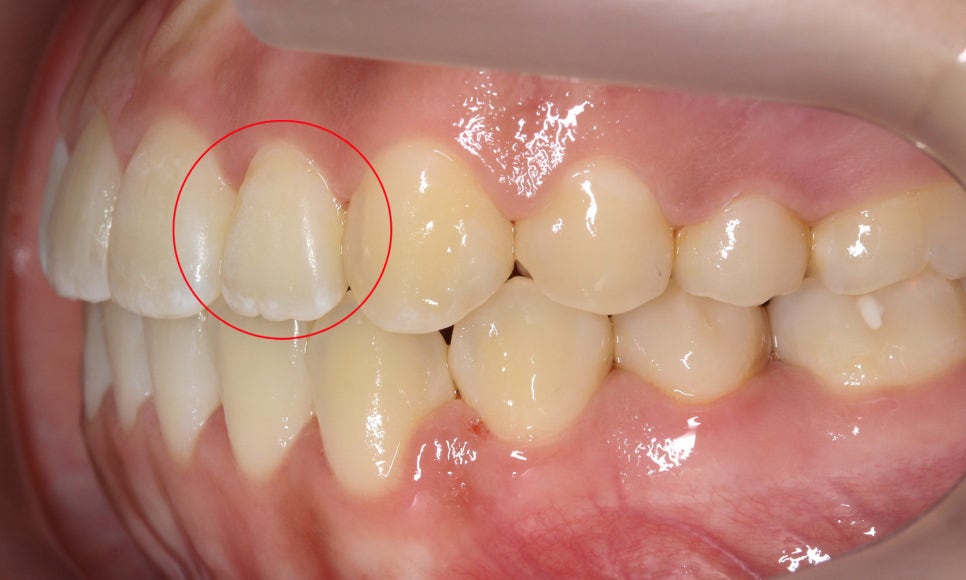

반대쪽 측절치 역시

길이가 짧아서 치아 끝이

거의 마모되지 않은 모습입니다~

윗니의 안쪽 면을 보면

작은 앞니(측절치)의 크기가

주변 치아보다 확실히 작은 모습인데요,